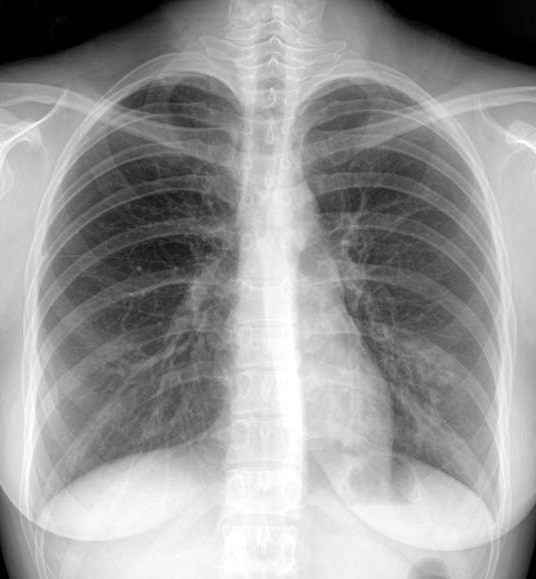

F/27

C.C : 2°³¿ù ÀüºÎÅÍ ¹Ýº¹µÇ´Â cough, sputum, rhinorrhea.

P/Ex. : wheezing on both lower lung fields.

Chest PA, Chest CT, Bronchoscopy , M-test was done.

Methacholine bronchial challenge test (+)